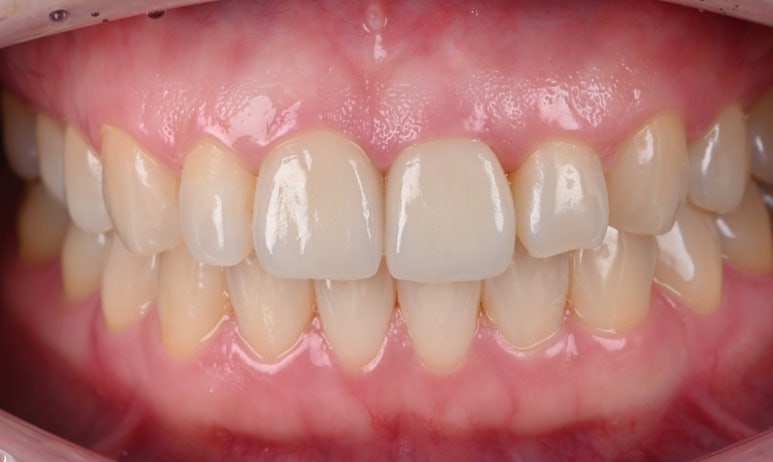

5. 최종 크라운 장착

새로 제작된 크라운을 장착합니다.

환자분께서 색상과 모양에 만족해하셔서 특별한 수정없이

치료를 마무리할 수 있었습니다.

25.09.11 치료 후